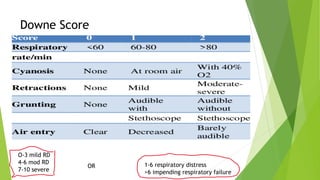

This document discusses respiratory distress and respiratory distress syndrome in neonates. It defines respiratory distress and describes the clinical signs. Various pulmonary and non-pulmonary causes are outlined. Respiratory distress syndrome, also known as hyaline membrane disease, is described in detail, including risk factors, pathophysiology, clinical presentation, investigations, complications, prevention, and treatment approaches like surfactant administration and nasal continuous positive airway pressure. The prognosis depends on gestational age and quality of care provided.